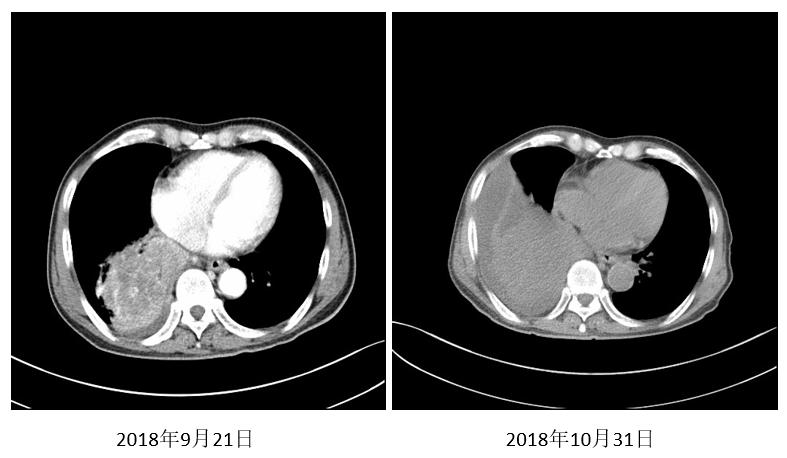

2018年10月23日行紫杉醇240mg D1+顺铂 30mg D1-D4方案化疗1周期。出现4度骨髓抑制伴粒缺性发热、胃肠道反应。同时复查胸部CT。

图2. 2018年10月31日复查(粒缺性发热)

2018年11月22日继续接受紫杉醇120mg D1 D8方案化疗1周期。再次出现4度骨髓抑制伴粒缺性发热,中止化疗。疗效评价未评价。